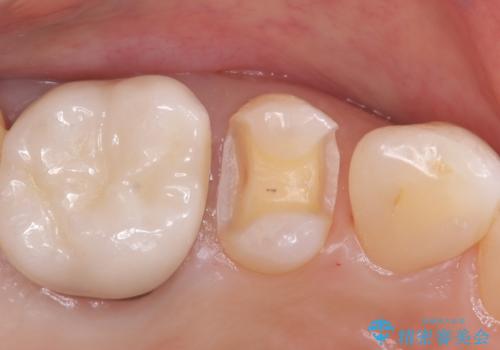

- 定期検診にてむし歯が見つかった患者さまです。

金属アレルギー体質とのことで、セラミックインレーにて修復治療を希望されました。